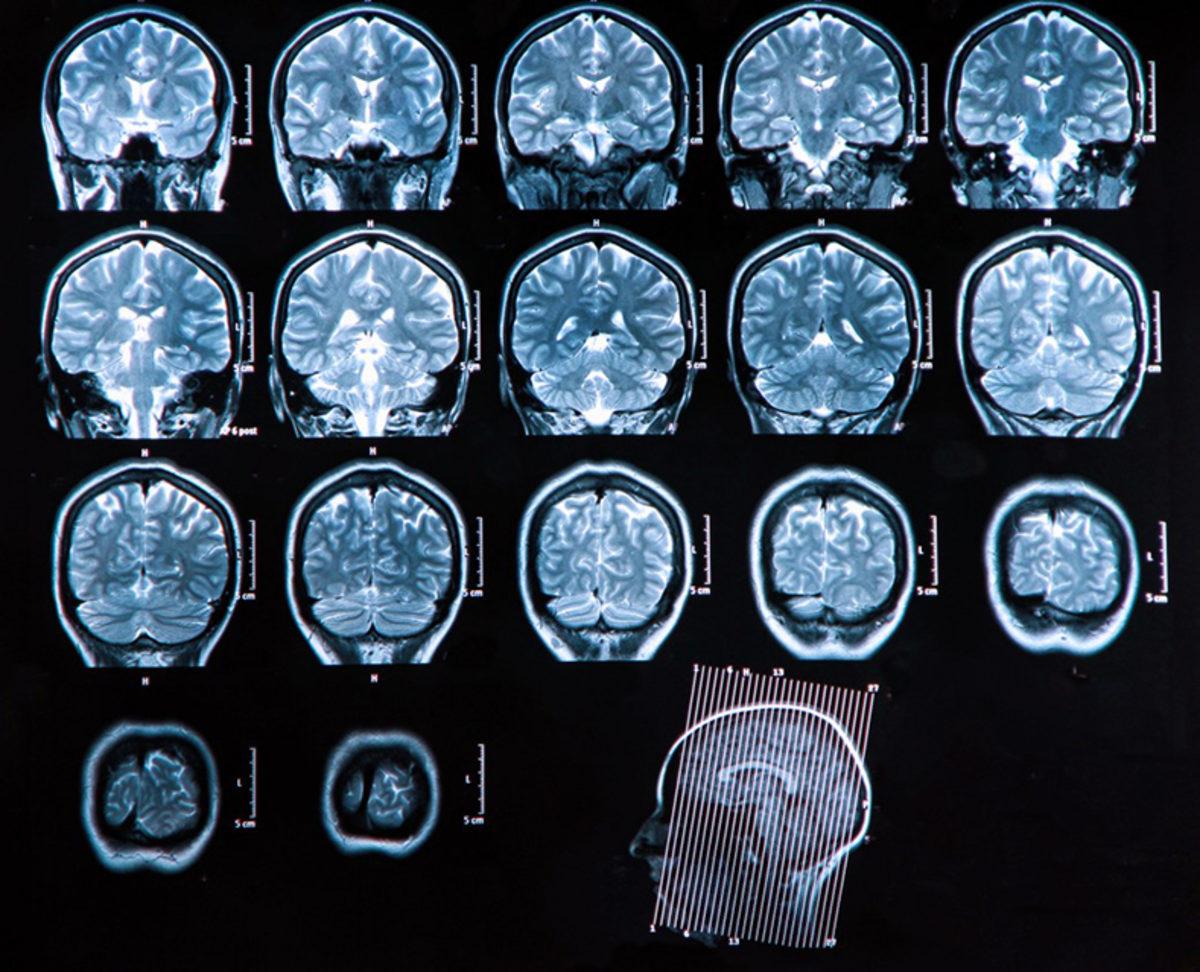

Pennsylvania Üniversitesi’nde yapılan yeni çalışmada üç kıtadan şizofreni hastalarının 300’den fazla MRI beyin taraması HYDRA adı verilen yeni bir makine öğrenme yöntemi ile analiz edildi. Makine öğrenme ile yapılan analiz sonuçları, bazı beyin bölgelerinde düşük miktarda gri madde bulunduğu yönündeki görüşlere meydan okuyor.

Yapılan analizde, şizofreni hastalarının yaklaşık yüzde 40’ının nispeten normal gri madde hacimleri gösterirken, şizofreni hastalarının önemli bir miktarı sağlıklı kontrol grubunun beyin taramalarına kıyasla, striatum adı verilen orta beyin bölgesinde gri maddede küçük de olsa artış gösterdi.